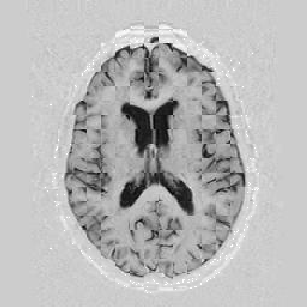

The results are shown for another pair of images in Figure [*].

Figure: Multi-scale NRR. From left to right, top then bottom: before NRR; after 5 iterations of NRR at level 2; after another 5 iterations of NRR at level 1.